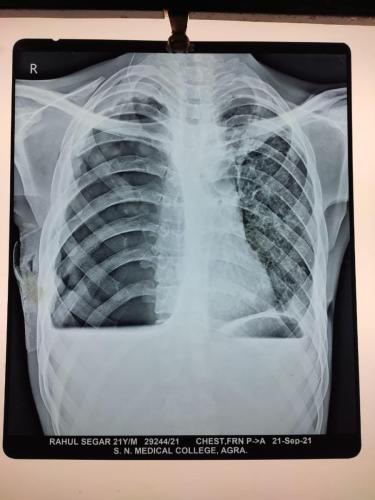

Photo Gallery Dr. Monika Gupta - Photo Gallery 7 5 2 8 6 Dr. Atul Kumar Gupta - Photo Gallery « ‹ of 3 › » Video Gallery